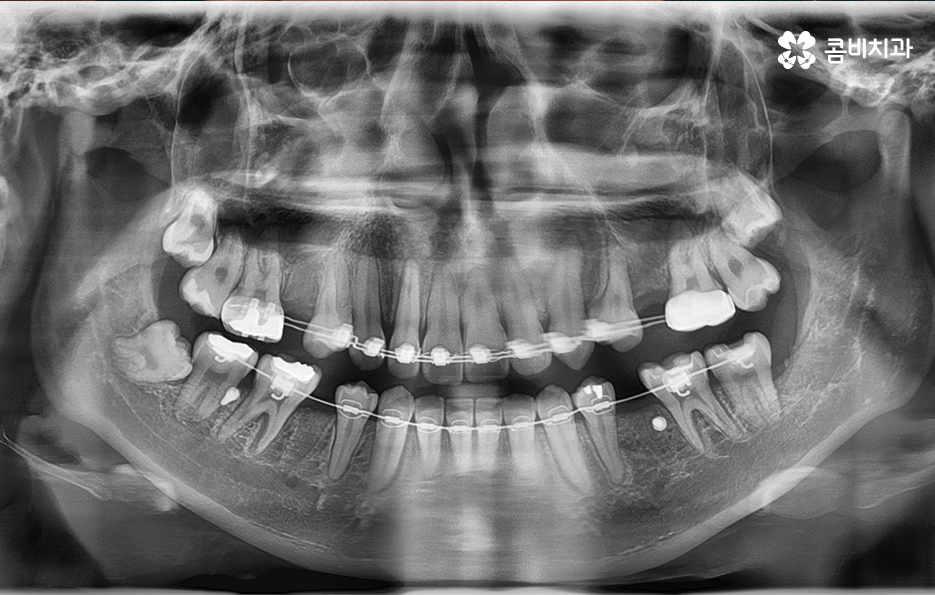

엑스레이에서 동그라미를 그린 4군데를 발치하여 교정이 진행된 사례

위 환자분의 사례는 현재 치열 상태와 골격, 얼굴형을 정밀

검진하여 시술 후 결과에 대한 시뮬레이션을 하였을 때

치열뿐 아니라 돌출입의 개선을 함께 목표로 진행이 되었기

때문에 콤비교정 전에 발치를 하게 된 케이스입니다.